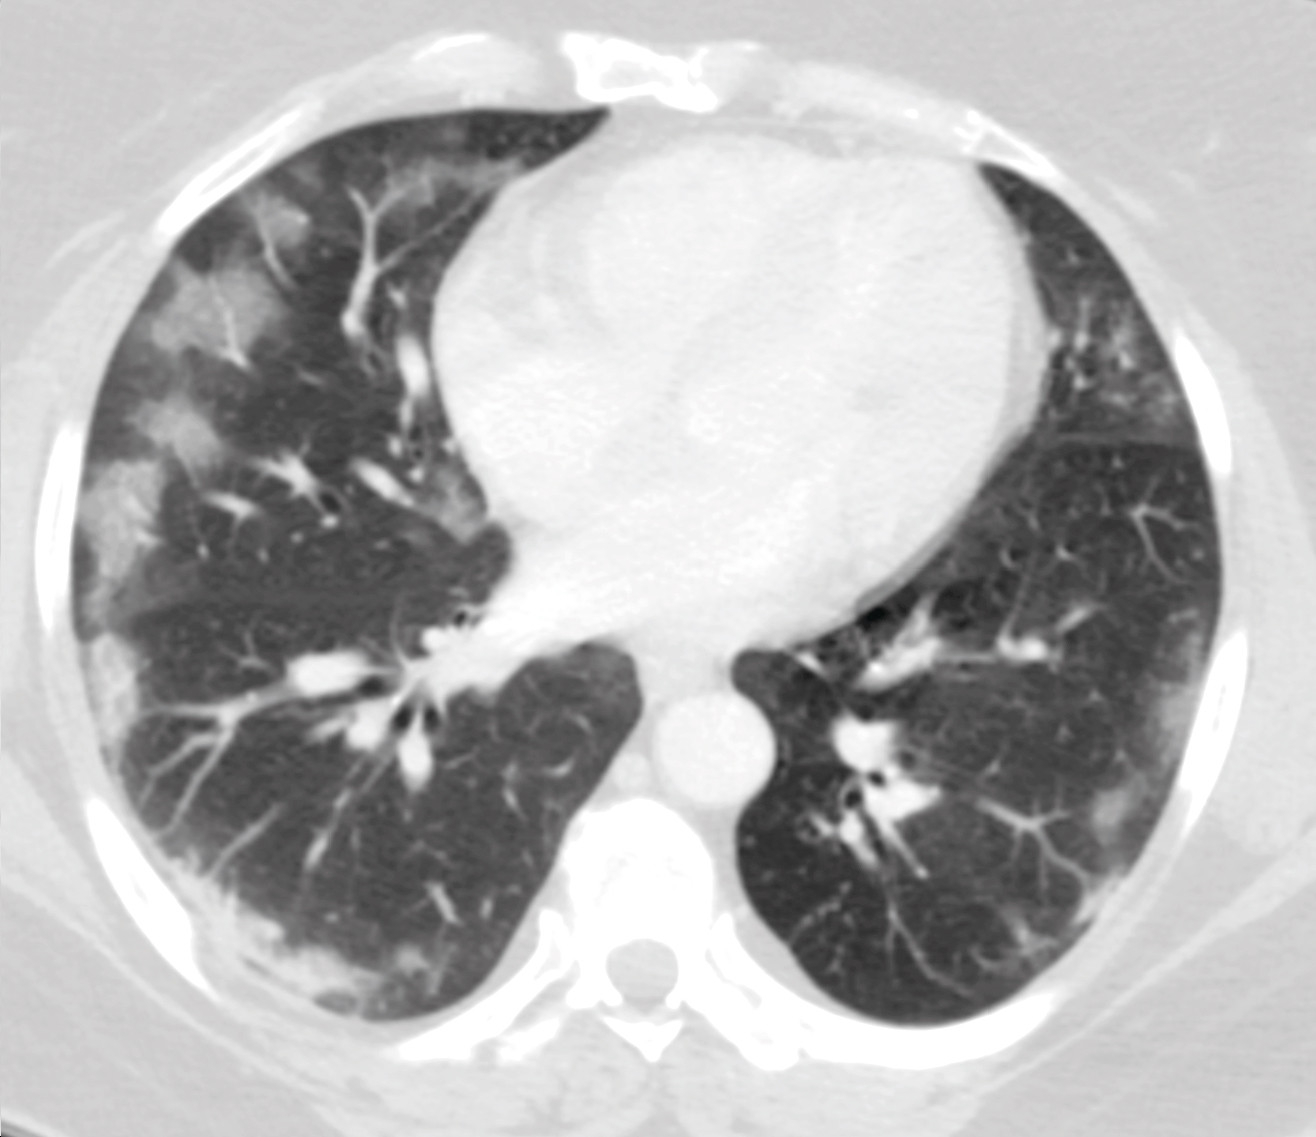

Det ble rekvirert en ultralydundersøkelse av lever og galleveier, men ettersom pasienten var overvektig og flere radiologer var i karantene på grunn av den pågående koronaepidemien, valgte man å endre dette til en CT-undersøkelse med intravenøs kontrast. Ved CT av abdomen og bekken ble det ikke påvist aktuelle funn i buken, utenom gallestein som var kjent fra tidligere. Det var ingen radiologiske tegn på kolecystitt. På basale lungesnitt ble det imidlertid sett løst mettede fortetninger perifert i begge lunger samt enkelte områder med mer konsolidert preg. Det var ingen pleuravæske. Radiologen vurderte at funnene kunne passe med viral eller atypisk pneumoni (figur 1).

Enkelte pasienter med covid-19 debuterer imidlertid med andre symptomer. I løpet av de siste to ukene har vi i vårt akuttmottak hatt ytterligere fem pasienter med tilsvarende symptombilde, der covid-19 har blitt bekreftet ved sanntids-PCR. Det dominerende symptombildet hos alle disse var magesmerter, der enkelte også hadde smerter i nedre del av buken. I tillegg rapporterte de om nedsatt matlyst, kvalme og oppkast. Noen hadde også diaré. Ingen hadde nytilkomne luftveissymptomer. Alle ble utredet med CT abdomen som ledd i utredningen av magesmerter, der bildene viste typiske funn for covid-19 i lungene (figur 2).